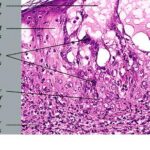

Herpes simplex = العقبول البسيط